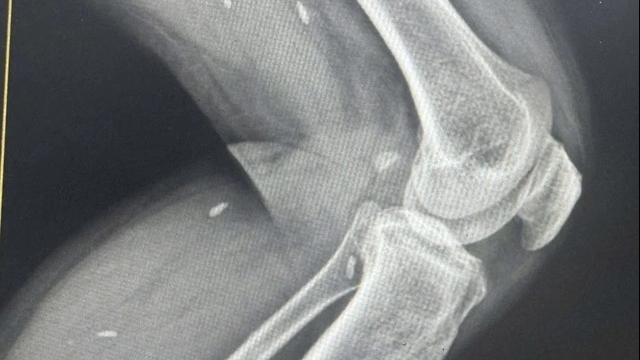

Kết quả chụp phim CT Scan xương thái dương khẳng định bệnh nhân bị viêm tai xương chũm có khối cholesteatoma lớn trong xương chũm.

Sau đó, người bệnh được phẫu thuật tiệt căn xương chũm ngay, lấy bỏ toàn bộ khối cholesteatoma có kích thước khá lớn chiếm toàn bộ xương chũm đã có xuất ngoại thành trên ống tai ngoài. Sau khi được phẫu thuật, người bệnh hết hoàn toàn triệu chứng đau đầu và mất ngủ.

Rất may mắn, khối tổ chức cholesteatoma chưa gây các tổn thương tới các cơ quan quan trọng ở trong tai và vùng xung quanh.

Theo bác sĩ Trần Phương Thảo - Khoa Tai Mũi Họng, Bệnh viện Trung ương Quân đội 108, trong các trường hợp như bệnh nhân T.M.T hay các trường hợp chẩn đoán khó, các phương pháp thăm dò chẩn đoán hình ảnh hiện đại như chụp CT scan có thể giúp khẳng định bệnh.